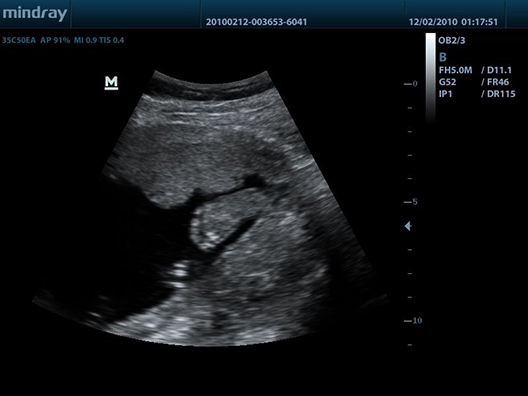

• Конвексный датчик Mindray 35C50EA

Mindray DP-50 - портативный УЗИ аппарат, который является ярким представителем семейства Mindray. Он представляет собой ультракомпактное переносное устройство для проведения УЗИ-сканирования пациентов на дому или в машине скорой помощи. Аппарат оснащен черно-белым экраном и считается одним из лучших в своем классе. Он отличается высокой проникающей способностью УЗ-луча, которая обычно характерна для стационарных аппаратов.

Благодаря оптимальному 15-дюймовому экрану, впечатляющей технической оснащенности и портативной компактности, Mindray DP-50 нашел свою целевую аудиторию практически во всех сегментах современной медицины. Двухуровневая панель управления с трекболом и складывающимся экраном позволяют удобно и безопасно транспортировать систему, подобно ноутбуку. Возможности клинических исследований дополняются датчиками, которые можно приобрести дополнительно: линейные, конвексные, микроконвексные, внутриполостные, биплановые. Все зависит от ваших задач.